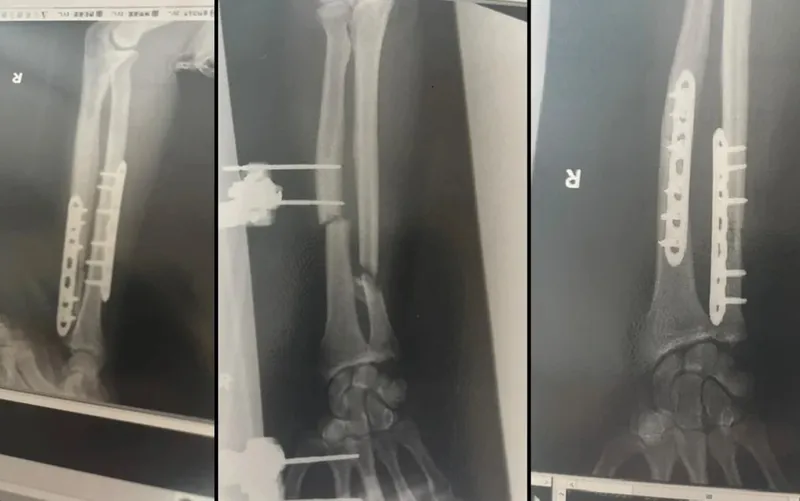

"Одним укусом моя рука была уничтожена", – рассказал журналистам Холлоран.

Несмотря на боль и потерю крови, бегун сумел подняться и пройти около километра, пока не добрался до места, где его нашли спасатели. В больнице ему сделали три операции, включая пересадку кости из бедра, чтобы восстановить поврежденную руку.